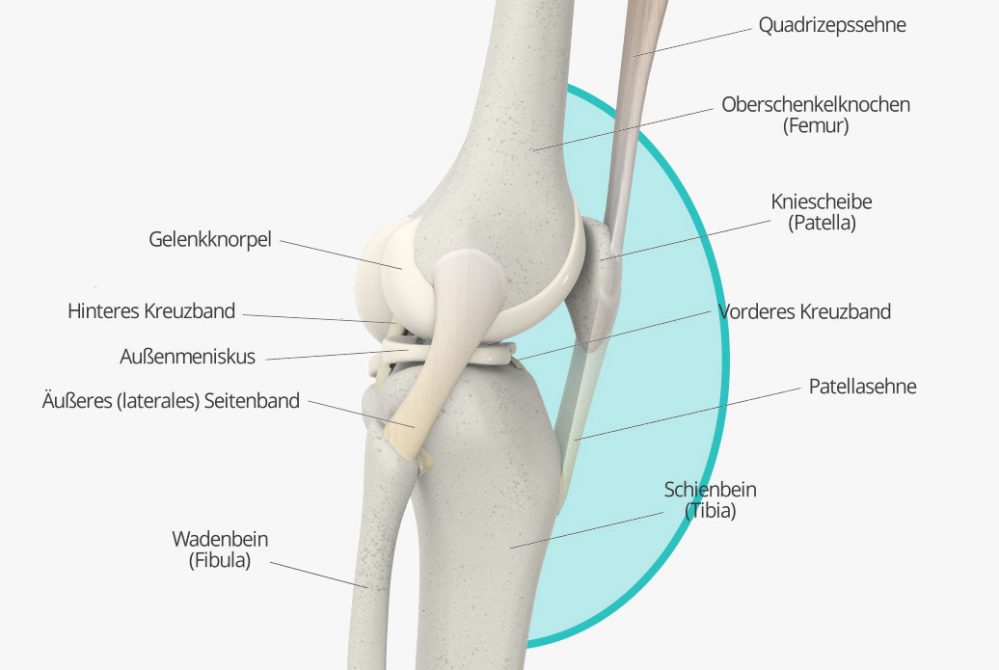

Knieschmerzen, die an der Vorderseite des Knies auftreten, stehen zumeist mit der Patella, (Kniescheibe) in Zusammenhang. Schäden an und Probleme mit der Kniescheibe können diverse Ursachen haben. Wie so oft, kann der Schmerz vielfach auf Überbeanspruchung oder Fehlbelastung – oder Verschleißerscheinungen in deren Folge – zurückgeführt werden. Doch auch Krankheitsbilder wie das Plicasyndrom oder eine so genannte Patellaluxation können Ursachen für Beschwerden vorn am Knie sein.

Manchmal lässt sich der gefühlte Schmerz auch direkt der Kniescheibe zuordnen, zum Beispiel, weil der Schmerz direkt in Zusammenhang mit einer Bewegung der Kniescheibe steht. Im Prinzip kommen hier als Ursache all die Krankheitsbilder in Frage, die auch allgemein bei Schmerzen vorne im Knie mögliche Diagnosen darstellen. Dazu zählen insbesondere das Plicasyndrom, die Patellaluxation sowie Fehl- und Überbelastung und Verschleiß bis hin zur Arthrose. Doch auch etwa ein Bruch der Kniescheibe kommt als Ursache in Frage. Ein Orthopäde kann auch hier die Ursache leicht über eine Anamnese, körperliche Untersuchung sowie in der Regel auch bildgebende Verfahren feststellen.

Achten Sie beim Sport auch auf Zeichen Ihres Körpers, und versuchen Sie, Fehlhaltungen ebenso zu vermeiden wie Überbeanspruchung. Das mindert das Risiko von Sportverletzungen wie Kreuzbandriss oder Meniskusschäden. Sind Ihnen Fehlstellungen wie ein Beckenschiefstand oder eine Fußfehlstellung bekannt, weil diese bereits von einem Arzt diagnostiziert wurden, sollten Sie diese gegebenenfalls korrigieren lassen, um Folgeschäden zu vermeiden.